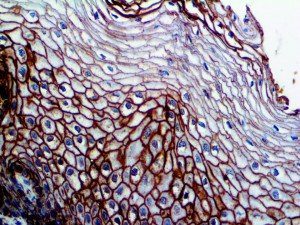

This activation induces inflammatory monocytes to highly express IL-6, starting a localized and then systemic cascade effect that results in hyperproduction of IL-6, which accelerates the inflammatory process. Because IL-6 also increases vascular permeability, excessive levels cause blood vessels to become very leaky. This, along with clotting factors released from vascular endothelial cells, stimulates the coagulation cascade, resulting in microthrombosis (tiny clots), which leads to ischemia and tissue death of the kidney, intestines, heart, liver, brain and extremities.